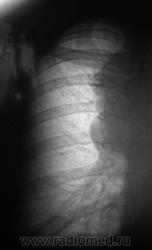

Флюорограмма - 2009 год.